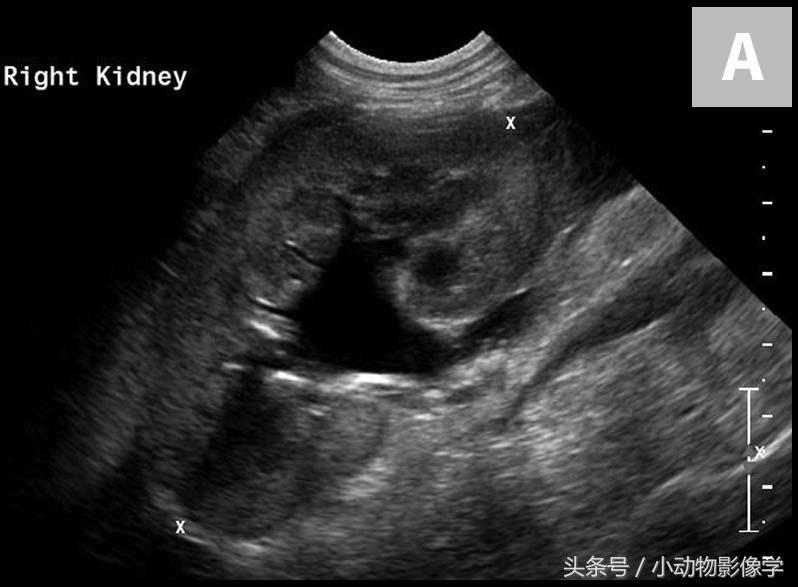

与输尿管结石相关的临床症状可以是长期非特异性症状,或急性或慢性肾功能衰竭。肾积水则高度提示输尿管阻塞(图6)。

图6A、一只大麦町犬轻度至中度的右肾盂积水和近端输尿管扩张。

图6B、这是导致图6A中犬尿道梗阻和肾盂积水的右侧输尿管结石(准星之间)的超声图像。注意输尿管结石附近的输尿管扩张(三角箭头之间)。